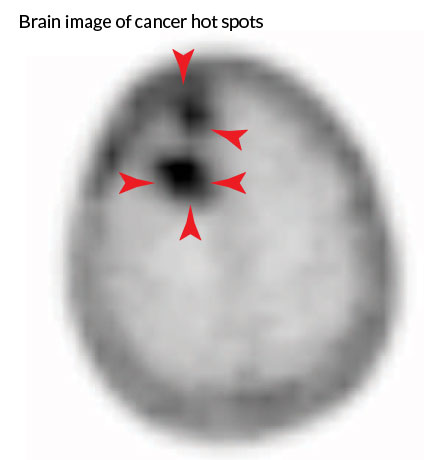

By injecting the amino acid glutamine that’s been tagged with a tracer compound into patients with brain cancer, scientists have devised a technique that might enable doctors to spot growth of such tumors with high accuracy.

In six glioma patients, brain scans revealed that while aggressive brain tumors took up the tagged glutamine readily, stable tumors did so only minimally, if at all. The imaging technique might enable doctors to more clearly track brain cancer growth, the authors say.